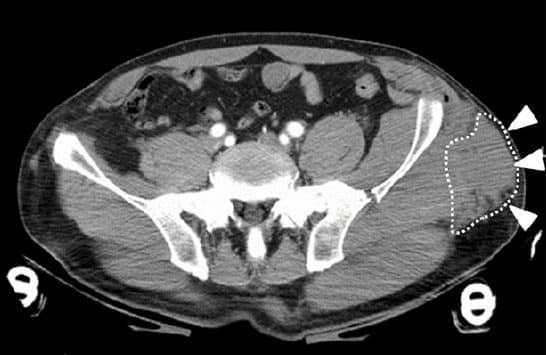

إصابات جلدية مثل آفة موريل-لافاليه (Morel-Lavallée)

آفة موريل-لافاليه

هي إصابة انفصال داخلية يحدث فيها انفصال الجلد والأنسجة تحت الجلد عن اللفافة العميقة، ما يؤدي لتجمع سائل يمكن أن يصبح مزمنًا أو يلتئم تلقائيًا. تشاهد غالبًا في إصابات الرضوض عالية الطاقة حول الحوض والفخذ.